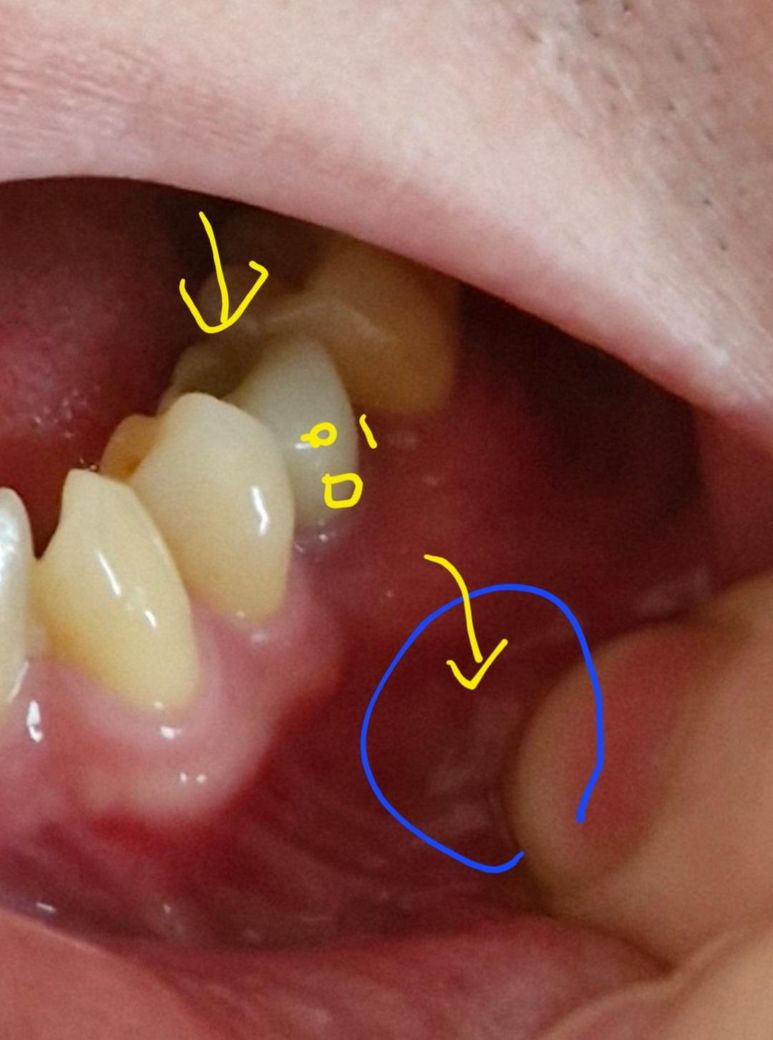

잇몸 아래쪽 입술살과 이어진부분이 통증이 있어요

사진에 동그라미 친 부위께에 동글동글 멍울같은게 있는데 여기가 누르면 아프거든요

아랫입술 살갗과 안쪽깊은잇몸에 이어진 부분이라고 해야하나

이쪽에 동글동글..누르면 만져지는곳이 있는데

여기가 단단하고 일부러누르면 아프네요 급소누르면 아프듯..

사진은 왼쪽치아쪽인데

해당 위치에 뼈이식없이 임플란트한지

2년넘어가는데요

혹시 임플란트때문에 신경이나..뭐 그런 문제때문인걸까요

• 1번 째 사진

사진상으로 보면 구내염일 가능성이 높아 보입니다. 최대한 저부위에 자극이 가지 않도록 하면 시간이 지나면 괜찮아 지는거니 너무 걱정하지마세요.

해당 임플란트가 문제일지 아니면 인접한 다른 치아가 문제일지는 엑스레이찍어보고 검사를 해봐야 합니다. 임플란트가 문제라면 임플란트 크라운을 잠시 분리해서 빼두고 증상을 지켜봐야 합니다. 증상이 그래도 지속되면 픽스쳐 제거후 재식립 해야 할 수도 있습니다.